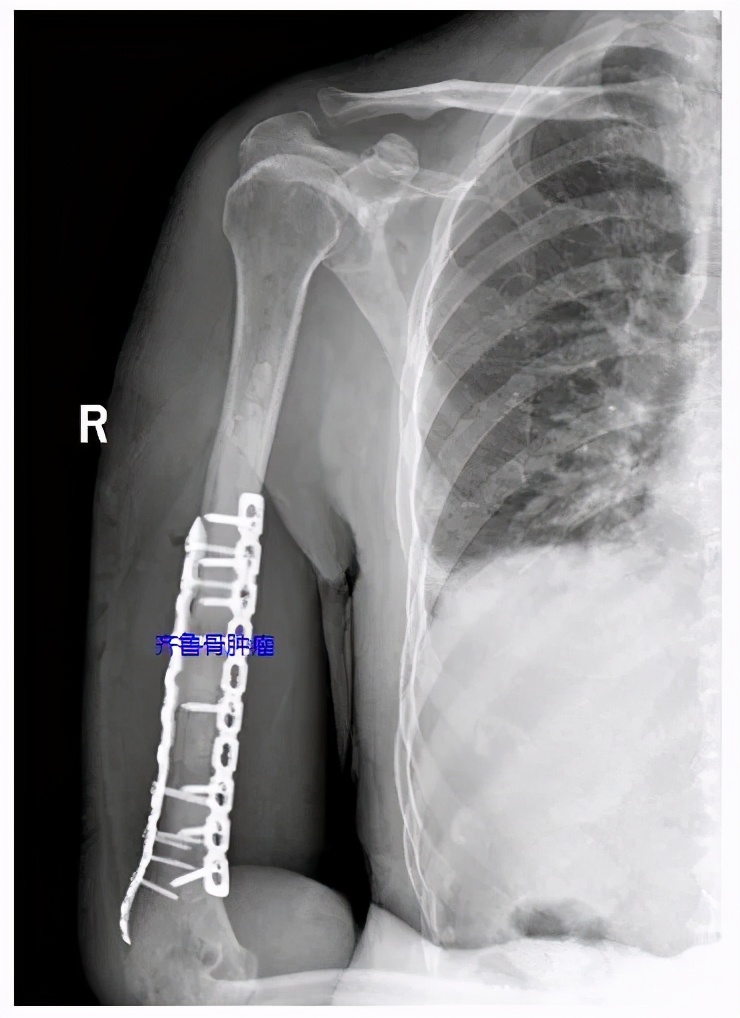

医生团队考虑3D打印假体重建手术对该患者来说创伤较大,术后功能恢复慢,最终放弃了该方案,经过综合考虑选择了借用微波技术消除肿瘤,进一步用骨水泥填充钢板内固定的方式重建肱骨。经过与患者及家属充分沟通及精细的术前准备后,李建民教授带领团队为患者进行了手术,术中依靠精湛的手术技术保护好桡神经,同时用微波针消融软组织包块和髓内病变,使其表面碳化,然后进行骨水泥填充和钢板内固定,重建肱骨。手术历时2小时顺利结束,术后第1天,患者桡神经功能正常;术后第4天,患者康复出院,这也符合我院骨科中心加速康复的理念(我院是国家卫生健康委加速康复外科首批试点医院)。

骨水泥填充及钢板位置良好